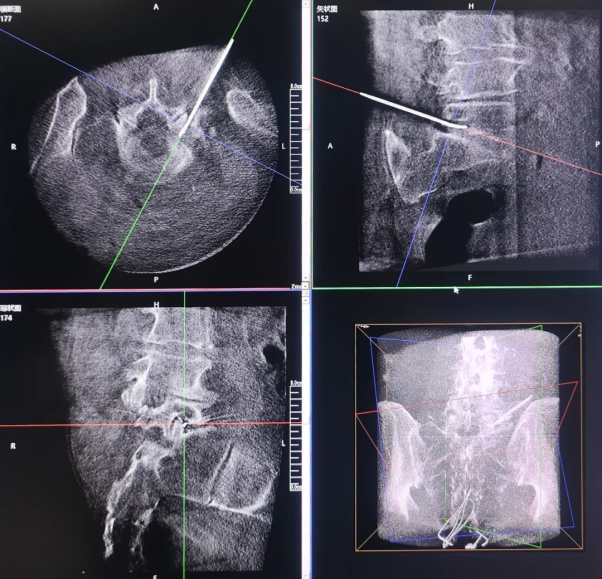

Radiofrequency Thermocoagulation of the Trigeminal Gasserian Ganglion

Radiofrequency Ablation of the Lumbar Dorsal Root Ganglion

Given that the primary targets in pain management procedures, such as nerves, spinal discs, and joint capsule, are deep-seated and often adjacent to critical structures like blood vessels and nerve roots, intraoperative 3D imaging is essential. It provides surgeons with a clear, three-dimensional view of the bony anatomy and deep tissue, significantly reducing the risk of nerve damage during puncture.

The 3D C-arm can generate intraoperative three-dimensional spinal images and CT-like cross-sectional views, providing physicians with a more comprehensive perspective for observation and clinical diagnosis.